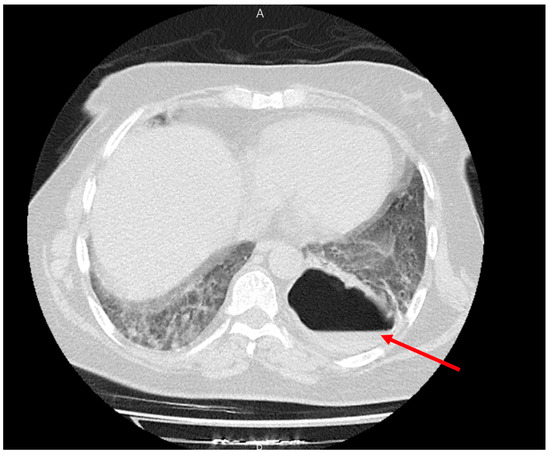

The patient underwent serum therapy and a standard treatment for gastrointestinal bleeding (GIB), including sufficient hydration, IV proton pump inhibitor (PPI) (pantoprazole 40 mg/IV/BID), upper GI endoscopy, and colonoscopy. The endoscopy results were normal, but a grade 4 hemorrhoid was reported. No bleeding hemorrhagic gross lesion was observed. A new lung CT was performed for the patient, which showed a cavity with a thick and irregular wall with an air-fluid level suggesting a pulmonary abscess in the left upper lobe (LUL). Bilateral diffuse GGO lesions with septal thickening, as well as mild bilateral effusion, were also observed (Figure 4). A pulmonary CT angiography was performed to rule out pulmonary thromboembolism (PTE), which showed no evidence of PTE.

Figure 4.

A cavity with a thick and irregular wall with an air-fluid level suggesting pulmonary abscess in the left upper lobe (red arrow). Bilateral diffuse GGO lesions with septal thickening as well as a mild bilateral effusion were also observed (blue arrows).